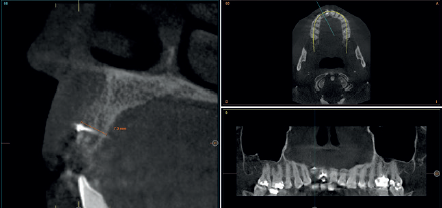

Para continuar con el estudio del caso se realiza un Cone-Beam donde poder observar tridimensional ente la posición del implante situado en posición 1.2. En los cortes seccionales se visualiza completamente situado hacia vestibular con una reabsorción casi completa de la cortical ósea de esta área, lo que explica los problemas de tejido blando subyacente. En la radiografía periapical se observa la posición del implante con respecto a los dientes adyacentes

(Figuras 5 y 6). Con esta imagen se procede a la apertura de un colgajo y la explantación del implante. Se retira también la corona situada en el diente 1.1 para poder realizar otra corona que servirá para apoyar el provisional en extensión para la zona del 1.2, mientras cicatriza la primera intervención. En este primer abordaje se coloca también un injerto en bloque obtenido de la rama mandibular que se fija con un microtornillo en la zona a regenerar donde se ha perdido la cortical vestibular. Una vez fijado y posicionado, se rellena alrededor del injerto en bloque con hueso particulado obtenido con un bone-scraper de la misma zona donante embebido en PRGF-Endoret para una mejor fijación y viabilidad celular (Figuras 7-9).